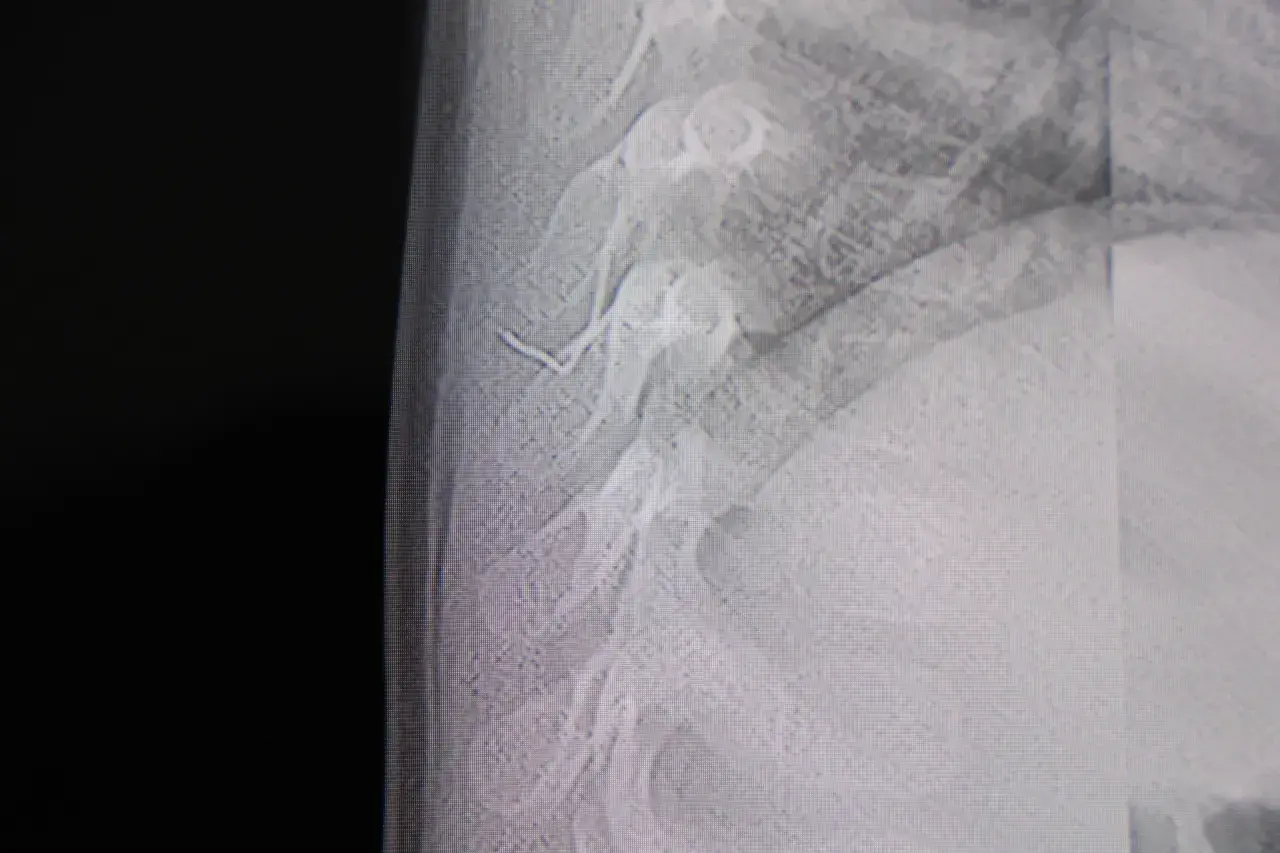

Beyin ve Sinir Cerrahisi Uzmanı Prof. Dr. İdris Altun tarafından yapılan tetkiklerde, yabancı cismin cilt altında, omurilik kanalına yakın bir bölgede olduğu ve akciğer zarına doğru ilerlediği belirlendi. Hasta, genel anesteziye alınmadan, lokal anestezi ve sedasyon eşliğinde ameliyata alındı. Yapılan müdahalede yabancı cisim tamamen çıkarıldı. Çıkarılan cismin, ince zımba teline benzer metal bir tel olduğu ve yaklaşık 2 santimetre uzunluğunda bulunduğu tespit edildi. Hasta, aynı gün taburcu edildi.

Konuya ilişkin açıklama yapan Prof. Dr. İdris Altun, "Sırtında yabancı bir cisim olduğu söylenmiş ancak çıkarılamayacağı ve 8 yaşına kadar beklenmesi gerektiği ifade edilmişti. Bize başvurduğunda yaptığımız tetkiklerde, cilt altında, omurilik kanalına çok yakın ve akciğer zarına doğru ilerleyen bir yabancı cisim tespit ettik. Hastamızı tamamen uyutmadan, lokal anestezi ve sedasyon eşliğinde müdahale ederek lezyonu tamamen çıkardık. Çıkardığımız cismin ince zımba teline benzer, yaklaşık 2 santimetre uzunluğunda metal bir tel olduğunu gördük. Bu yabancı cisim alınmasaydı, bölgede enfeksiyon gelişebilirdi. Enfeksiyon sonucu omurilik kanalında ciddi hasarlar oluşabilir, çocuk büyüdükçe cismin hareket etmesine bağlı olarak omurilikte zedelenmeler meydana gelebilirdi. Ayrıca yana doğru ilerleyerek akciğer zarına ve akciğere batma riski vardı. Bu da enfeksiyona ve ilerleyen süreçte tümörle karışabilecek tablolara neden olabilirdi. Şu an hastamız gayet sağlıklı. Gerekli kontrolleri yaptık ve aynı gün taburcu ettik" dedi.